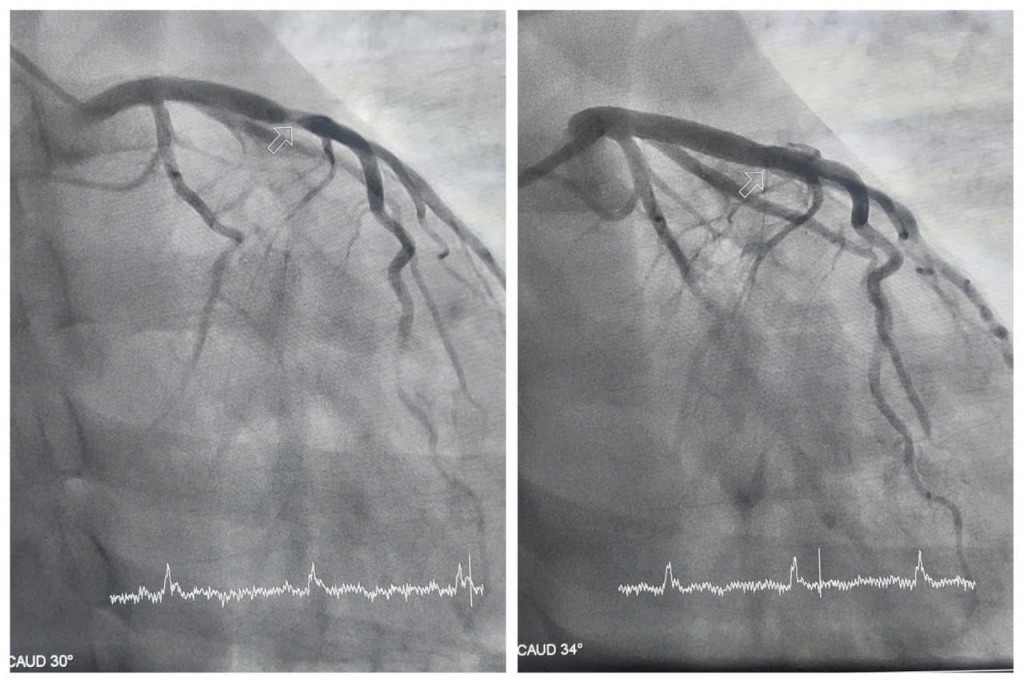

Bệnh nhân nhanh chóng được chuyển phòng can thiệp chụp mạch vành kiểm tra. Kết quả chụp cho thấy động mạch liên thất trước - một trong những nhánh mạch vành quan trọng nuôi dưỡng cơ tim, bị tổn thương nặng, hẹp khít 99%. Trước tình trạng nguy hiểm, các bác sĩ khoa Phẫu thuật và Can thiệp Tim mạch thực hiện can thiệp đặt stent nhằm tái thông máu nuôi tim, giúp người bệnh thoát khỏi tình trạng nguy hiểm.

| Hình ảnh hẹp tắc động mạch liên thất trước của bệnh nhân được can thiệp tái thông |